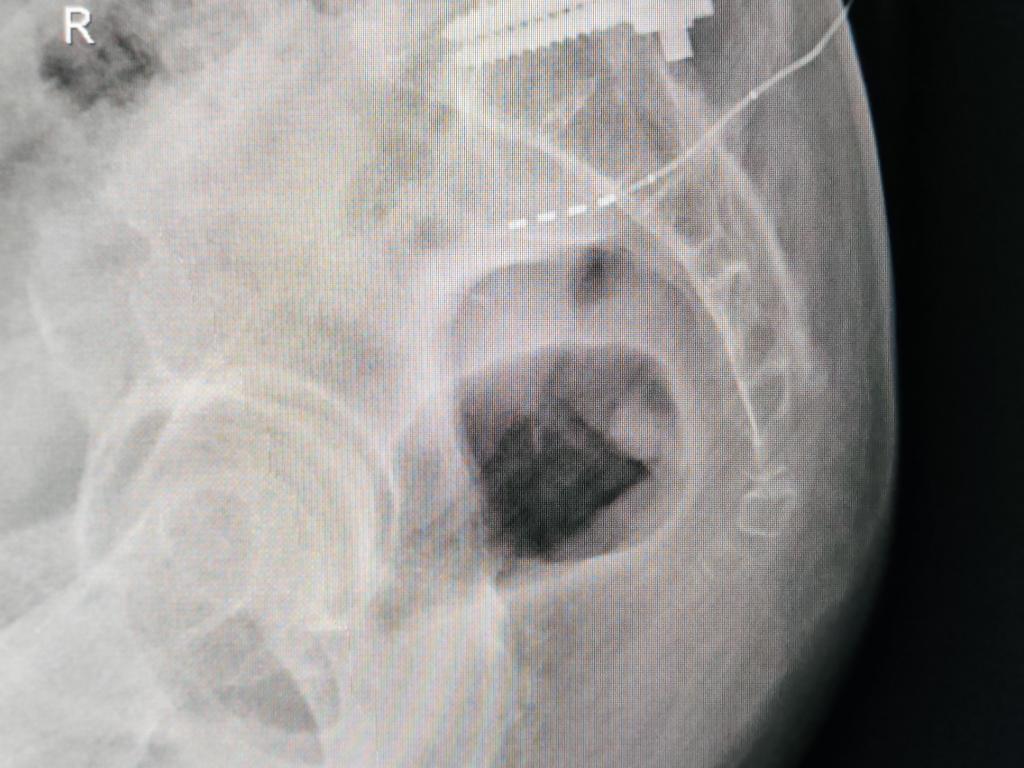

临时刺激器连接并开机 SNM Stage1术中24小时X线复查

骶神经调控疗法应用于一部分神经源性下尿路功能障碍及排便功能障碍性疾病治疗,须严格执行一期体验与二期手术两阶段。张阿姨目前接受SNM一期体验治疗,我们将通过一期体验治疗客观与主观疗效,确定患者是否适合二期手术以长期治疗。张阿姨术后24小时明确感觉肚子咕咕叫(肠活动增加)与排便感觉改善,计划认真体验治疗,如效果显著,将接受SNMstage2二期植入手术。